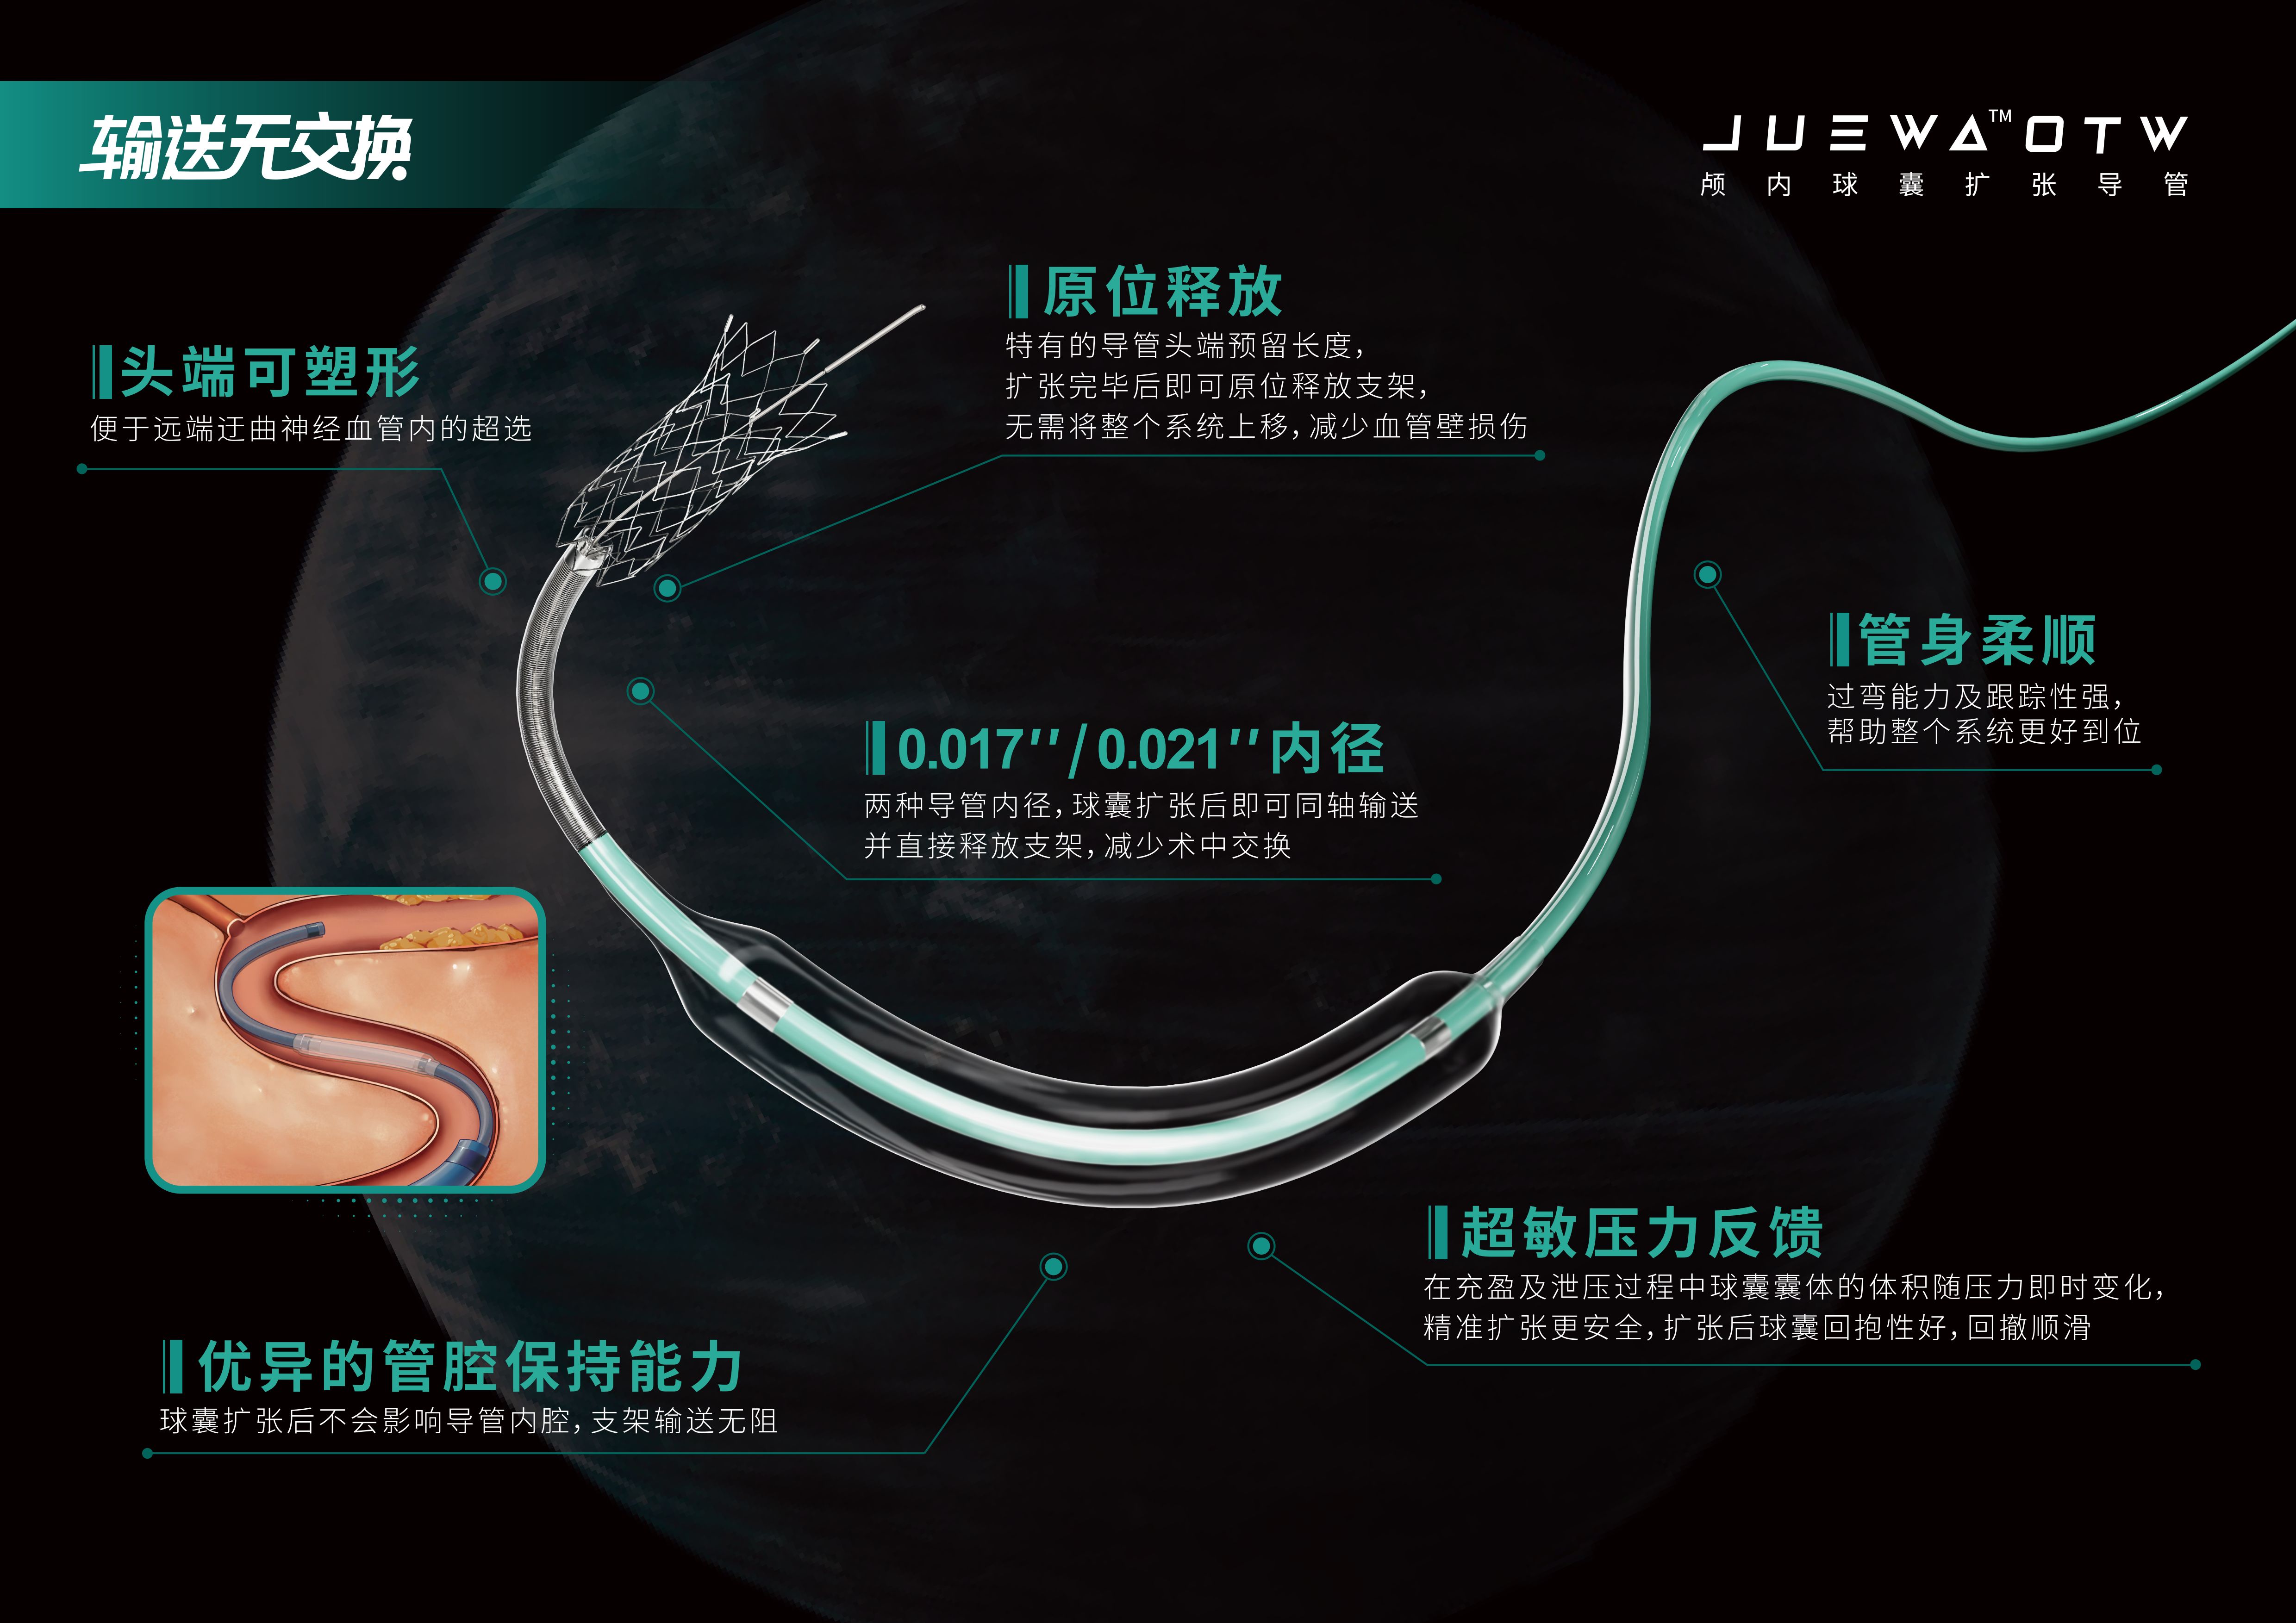

- [06-21]励楷Juewa OTW颅内球囊扩张导管在左侧颈内动脉虹吸段闭塞取栓术中的应用